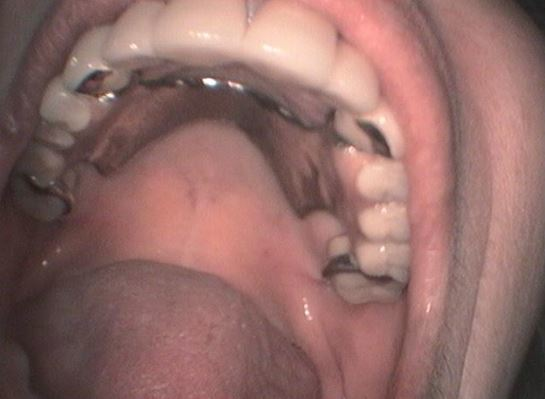

Στο ιατρειο μας κάθε χειρουργικο οδοντιατρικο περιστατικο καταγραφεται σε ολες του τις φασεις χρησιμοποιωντας μια συγχρονη ενδοστοματικη καμερα τελευταιας τεχνολογιας.Με τον τροπο αυτό διατηρουμε ένα πληρες αρχειο τοσο της αρχικης οσο και της τελικης καταστασης του ασθενους μας οσο και της εξελιξης της θεραπειας.Στο ιστορικο μας διαθετουμε ένα μεγαλο φωτογραφικο υλικο από οσα περιστατικα ελαβαν χωρα στο ιατρειο μας και είναι στη διαθεση σας ανα πασα στιγμη.Το αρχειακο μας υλικο θα ανανεωνεται συχνα με καινουργια περιστατικα. Στην παρουσα σελιδα μπορειτε να επισκεφτειτε μερικα από αυτα